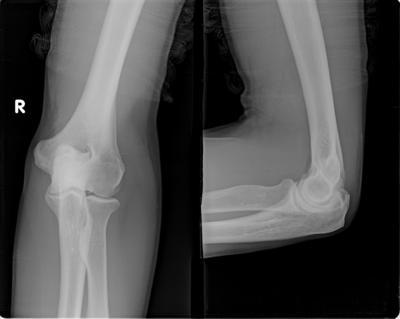

外周血白细胞计数升高,高达11×109/升(即11000/立方毫米),中性粒细胞比例也明显上升,高达85%,出现核左移现象。血沉和C-反应蛋白升高,血沉达87毫米/小时,C-反应蛋白在42毫克/升。RF(-)(类风湿因子)和ANA(抗核抗体)均为阴性。X线片显示膝关节软组织受损。

(图:患者肘关节疼痛,关节软组织受损)

(图:患者治疗后肘关节X线片示)